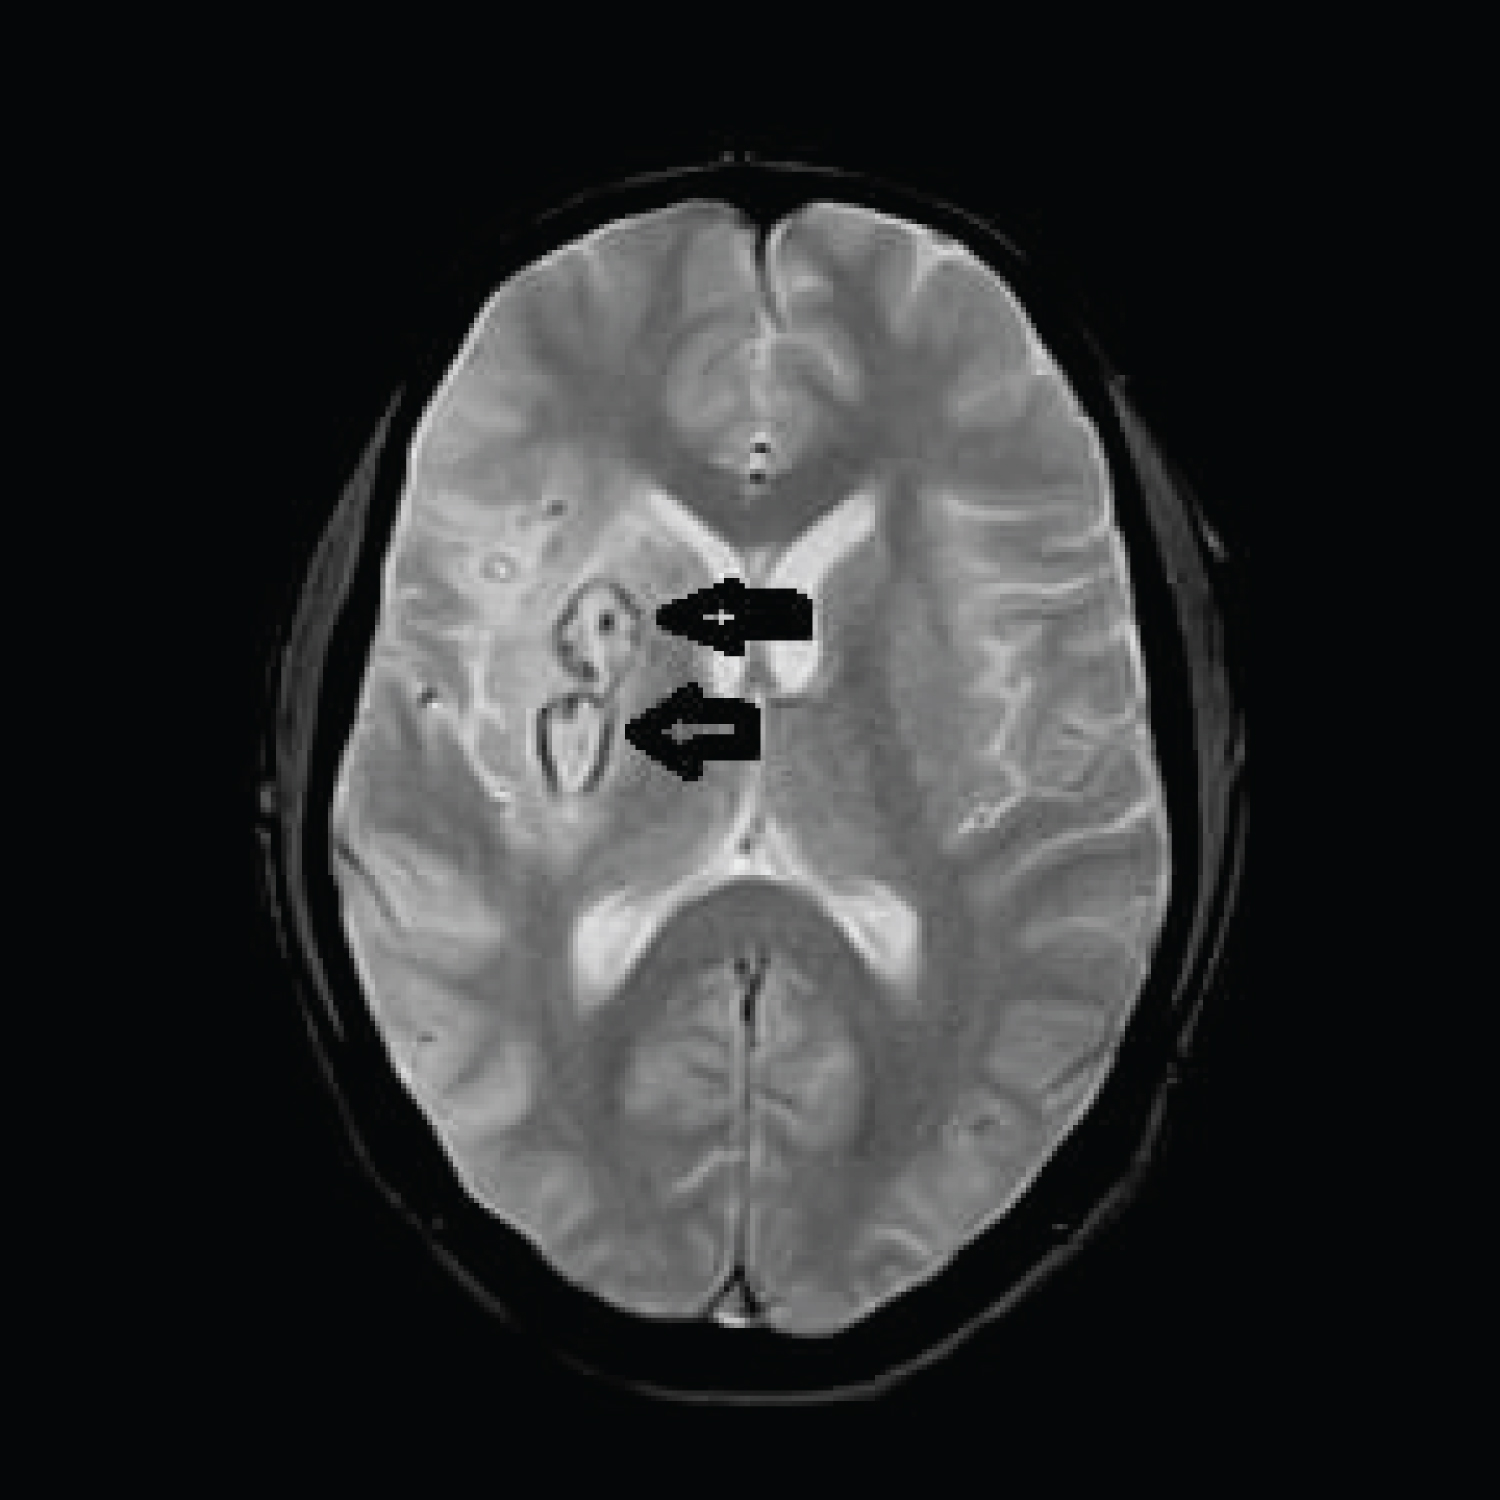

MRI brain done immediately showed patchy diffusion restriction in whole of the right middle cerebral artery (MCA) territory, however, only minimal insular involvement was seen on FLAIR sequence. Thus there was diffusion and FLAIR mismatch. MRA showed complete cut off at proximal right MCA consistent with large vessel occlusion (LVO) (Figure 1 and Figure 2).

Figure 1: MRI images showing FLAIR-Diffusion mismatch. View Figure Chart 1

MRI brain on day six post stroke showed a wedge shaped hypodensity in the right frontal and parietal region consistent with infarct with edema and mass effect with minimal midline shift 3 mm. Hemorrhagic change was seen in the area of the basal ganglia (Figure 3 and Figure 4).